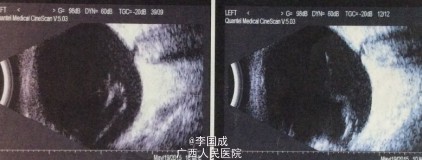

眼部检查: 视力:VOD:0.6 ,VOS:无光感,IOP:OD 34 mmHg,OS 19 mmHg,右眼无充血,角膜清,角膜背可见成簇状色素性kp,中央前房深度4CT,周边1/3CT,闪辉+,虹膜弥散萎缩,纹理欠清,虹膜后粘连,瞳孔对光反射—,晶体混浊,眼底窥不清。左眼无充血,角膜清,中央前房深度4CT、周边1/3CT,闪辉+,瞳孔对光反射-,欠圆,虹膜瞳孔缘后粘连,虹膜周边房角不规则前粘连,晶体混,眼底窥不清。

房角:双眼NⅣ(全粘闭)。